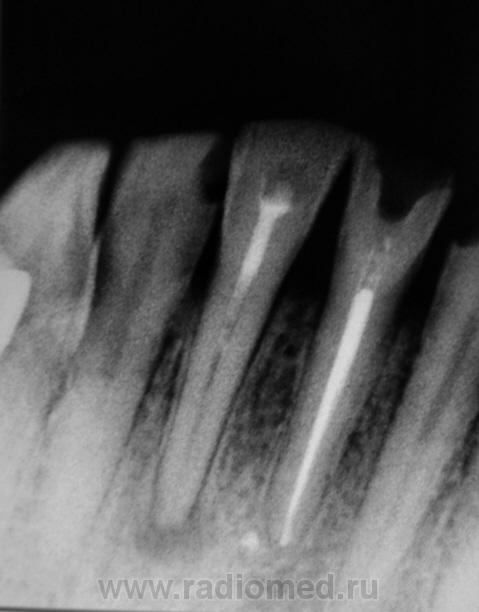

Начали лаборанты осваивать стомат - аппарат - "лапа паука".

Сегодня еще "наклепали". Слава богу, что описывать не приходится, а то возникли-бы ощутимые проблемы.

Правда, некоторые стоматологи не довольны, что аппарат заработал, да и снимок не выкинуть или затерять - все в компе.

Сначала мы хотели поставить стоматологам на этаж комп или даже два и "зациклить" их в нашу сеть. Я даже уговорил нашу администрацию, но после длительных "тары-бары" оказалось, что из стоматологов никто не умеет пользоваться компом, а главное - не хотят. Их сейчас очень устраивает, правда, весьма качественная распечатка на бумаге, но распечатка действительно очень качественная.